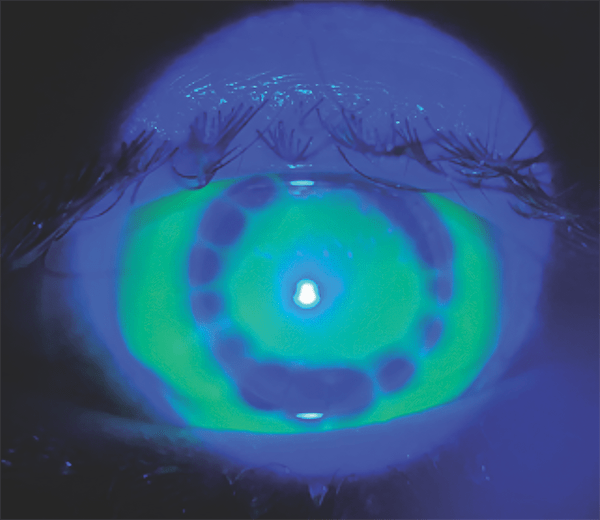

Fortunately, the versatility of the scleral lens design allows changes to two parameters simultaneously to achieve the desired clearances over the entire surface of the eye. This lens was redesigned by reducing the width of the second curve to avoid interference with the graft interface. In addition, overall SAG had to be increased by 200 microns to ensure clearance over the three crucial features of the cornea profile.

The inherent overall toricity of the scleral lens design was able to accommodate the circumferential cornea toricity caused by the asymmetric graft. The final fit resulted in a lens with adequate clearance over the apex, graft interface and sclera (Figure 2).